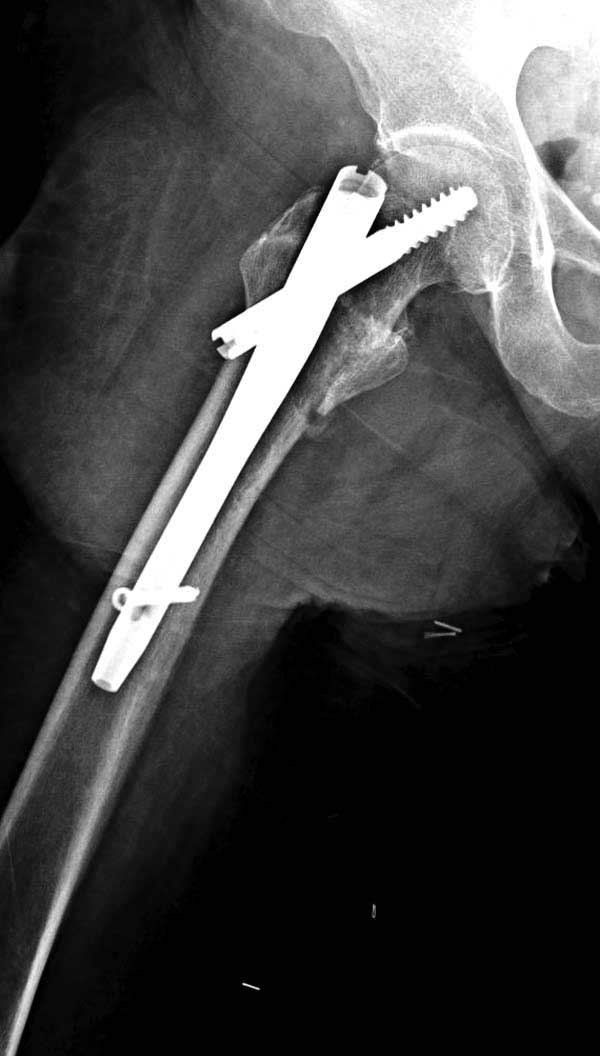

Первые снимки показывают технические погрешности установки DHS. Не была достигнута репозиция, конечность в флексии и шейка в ротации. Сегодня все меньше обращают внимание на параметры для оценки репозиции (S контуры Lowell в обеих проекциях и Garden Alignment Index, в норме 155 и 180 градусов), хотя такие простые тесты помогли бы дорепонировать смещение. Винт находится сзади в головке, что при нагрузке поменяет вектор и вместо компрессии в линии перелома срежет головку-Cut Out!

В зависимости от дистанции линии перелома и латерального кортекса надо использовать разной длины barrel, т.е. конец баррели не должен доходить до пределов перелома. Здесь конец длинного ствола упирается в медиальный фрагмент, что мешает созданию компрессии, а более короткий barrel создал бы запас для компрессии. В боковой пластине вместо 4х можно было ограничится двумя шурупами, потому что головка шурупа в 4.5 мм выдерживает давление до 350 кг.

Вторая операция- это фаза сохранения головки бедра. Желательно приложить все усилия и сохранить головку, но, как видно, “фиаско” продолжается. Здесь вместо нейтрализации сил между медиальной и латеральными сторонами была попытка удержать варус. Варус не удержать ни деротационными шурупами о котором говорили и не костными стружками вбитые в шейку, потому что вся нагрузка упирается в головку.

Как отметил Евгений, 95 degree Blade Plate Fixed Angle device  расчитана на восстановление взаимоотношении между головкой и диафизом, а все остальные фиксаторы (Gamma, Afifuxus и др.) работают за счет нагрузки в верхнем полюсе головки. Верхний полюс успели разрушить, и в головке единственное место, который смог бы удержать широкий клинок конструкции, это медиально-низкий сегмент. После установки клинка засчет дистракции можно удлинить конечность на 15мм, а добавленный в дефект ауто-графт закончил бы дело.